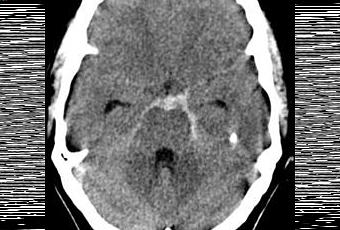

Image scanographique d'une hémorragie méningée (sous-arachnoïdienne)

Source iconographique: https://fr.wikipedia.org/wiki/H%C3%A9morragie_m%C3%A9ning%C3%A9e